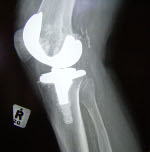

While the symptoms of arthritis are often similar, it is common for different types of arthritis to affect different joints in the body. For example, osteoarthritis is more likely to occur in the knees and hips than rheumatoid arthritis.